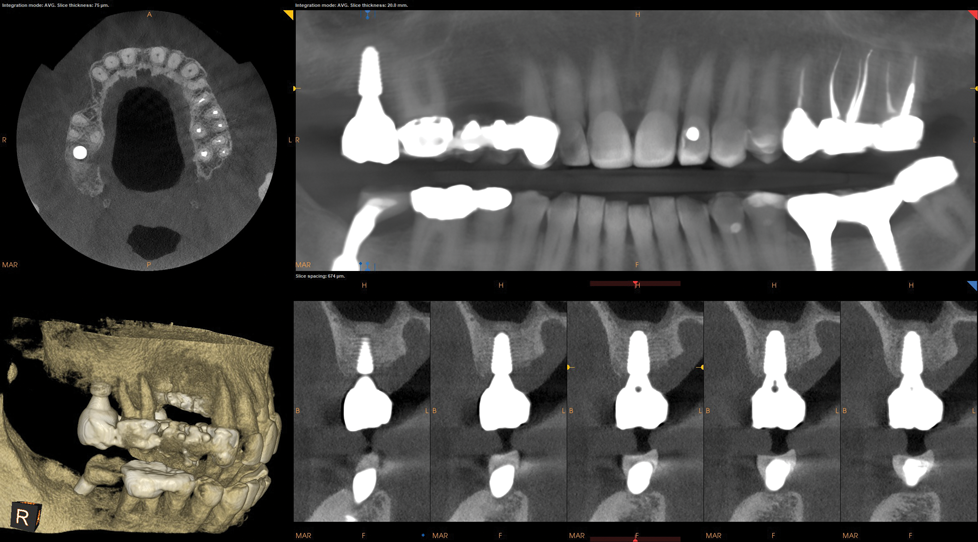

Upon evaluation of the CBCT using a metal artifact reduction (MAR) tool it was determined that either a short implant be placed or an internal sinus elevation procedure be performed to allow placement of a more robust implant. The CBCT showed less than 6 mm of residual bone height (Figure 5) available before the Schneiderian membrane of the maxillary sinus would be breached. After a review of available options, the patient elected to have the sinus elevation done and a longer implant placed with the use of guided surgery. Due to the limited access in the posterior of the oral cavity, the use of a static surgical guide might have proved difficult because of spatial and visual constrictions. Therefore, dynamic virtual navigation was chosen for this procedure.

Fig 5. CBCT revealed residual bone height less than 6 mm.

Figure 5